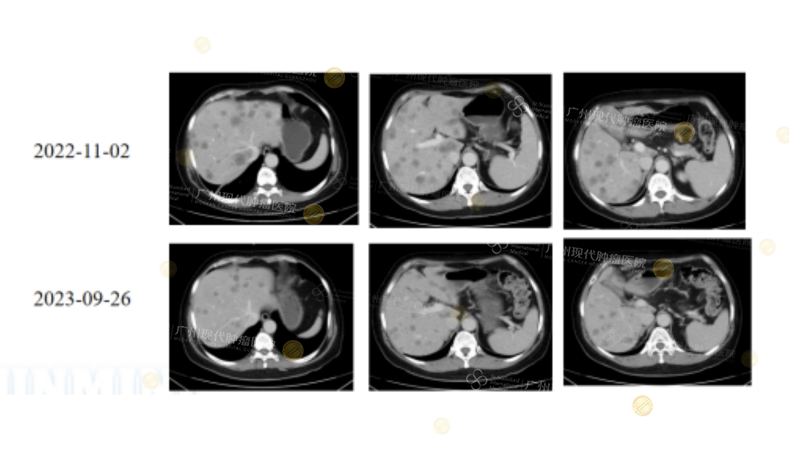

Breakthrough Efficacy in MSS CRLM Patients

Although MSS has traditionally been considered "difficult to benefit from treatment," cases from this hospital show:

(Note: 30-year-old male with multiple liver metastases after rectal cancer surgery (MSS/pMMR, NRAS G12D). After multiline biotherapy + targeted therapy + local treatment (Sintilimab+HAIC+Bevacizumab+MWA), liver metastases approached CR/NED, demonstrating breakthrough efficacy in MSS CRLM patients.)